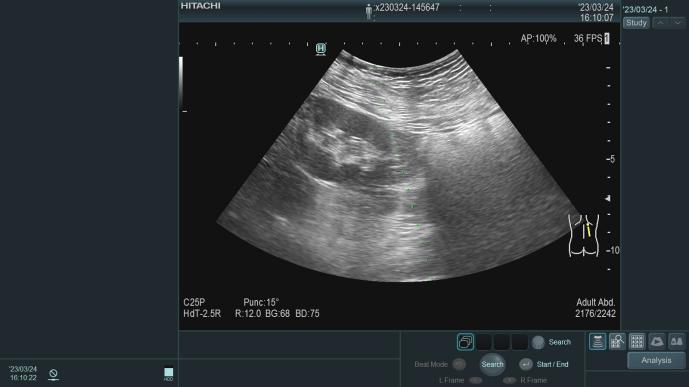

3.B超引导下肾穿刺活检术、腹透管植入术以及经皮内瘘血管形成术(PTA)、动静脉内瘘成形术以及透析血管通路的并发症诊治;

在广西较早独立编制的肾脏病专业科室,1995年开始应用超声引导下经皮肾穿刺活检术,协助诊断治疗各类肾脏疾病,积累丰富临床经验,如:急性肾小球肾炎、慢性肾小球肾炎、急性肾损伤、慢性肾衰竭、肾病综合征、IgA肾病、狼疮性肾炎、ANCA相关性小血管炎、糖尿病肾病、高血压肾病等疾病的诊断及治疗。

肾穿刺活检术